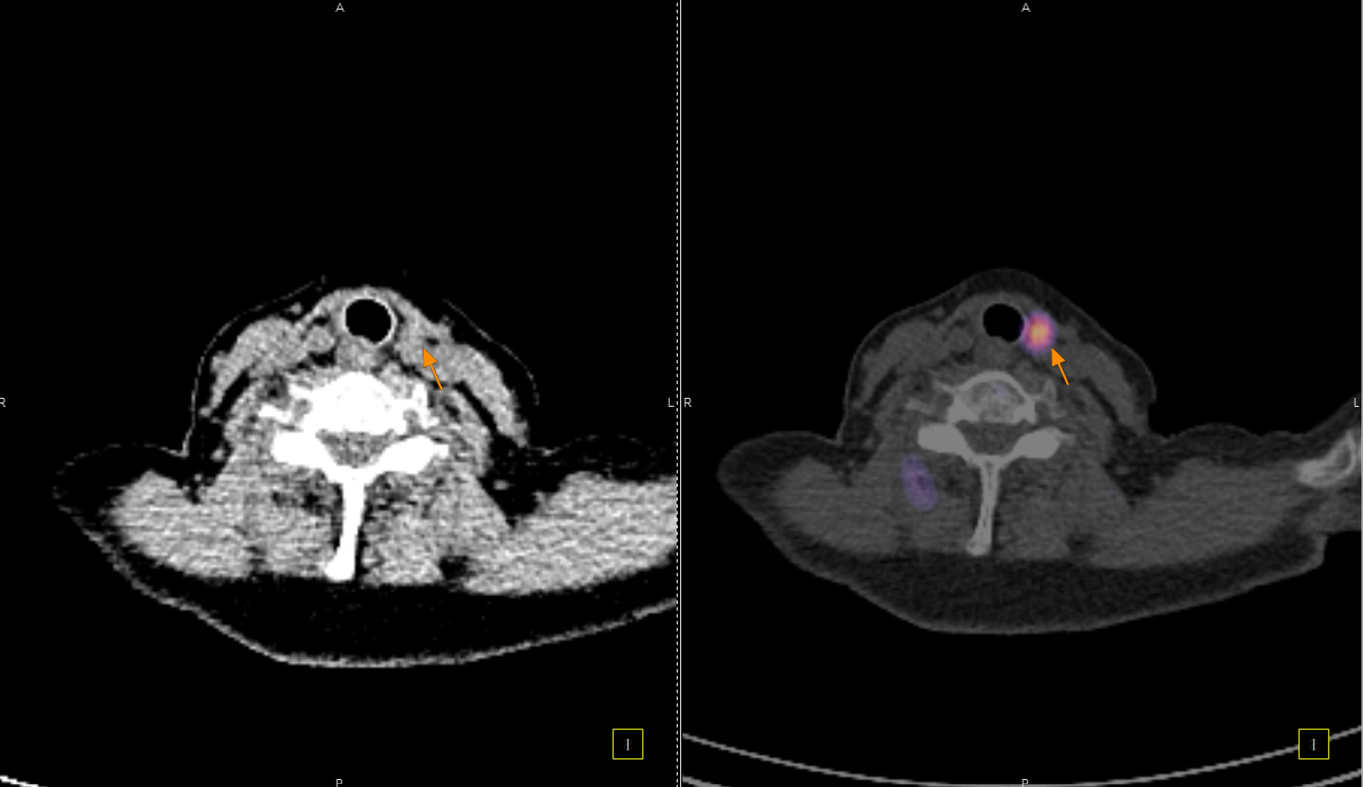

Οι περισσότερες διαγνωστικές εξετάσεις της Πυρηνικής Ιατρικής είναι γνωστές ως σπινθηρογραφήματα, τα οποία στη σύγχρονη εποχή πραγματοποιούνται με τη βοήθεια της γ-κάμερας (γ-camera) ή συστημάτων SPECT/CT, που επιτρέπουν απεικόνιση υψηλής ακρίβειας και λειτουργική ανάλυση σε μοριακό επίπεδο.

Πρόκειται για το πρώτο νοσοκομείο στην Ελλάδα που εφάρμοσε την επαναστατική SPECT/CT τεχνολογία με εμπειρία σε αυτή πάνω από 15 έτη.

Tο Νοσοκομείο ΥΓΕΙΑ είναι το μοναδικό με πάνω από 15 χρόνια εμπειρία στην SPECT CT Aπεικόνιση. Από το 2024 διαθέτει δύο υπερσύγχρονες τομογραφικές γ-κάμερες της Siemens – Symbia Pro.specta SPECT/CT with myExam Companion. Πρόκειται για συστήματα τελευταίας γενιάς που συνδυάζουν υψηλή απεικονιστική ακρίβεια, χαμηλή δόση ακτινοβολίας και πλήρη αυτοματοποίηση της διαδικασίας. Με την χρήση ειδικού σύγχρονου λογισμικού (SIEMENS SYNGO) εξασφαλίζεται η μέγιστη ποιότητα εικόνας. Ειδικότερα οι γ-κάμερες χαρακτηρίζονται από τα εξής:

Όλες οι μελέτες Πυρηνικής Ιατρικής πραγματοποιούνται με SPECT/CT μέθοδο στις 2 υπερσύγχρονες SIEMENS Pro SPecta. Από το δυσδιάστατο στο τρισδιάστατο, από την υπόνοια στη βεβαιότητα.

ΟΛΕΣ ΟΙ ΜΕΛΕΤΕΣ ΜΕ ΤΗ ΔΙΑΓΝΩΣΤΙΚΗ ΥΠΕΡΟΧΗ ΠΟΥ ΠΡΟΣΦΕΡΕΙ Η SPECT/CT ΑΠΕΙΚΟΝΙΣΗ